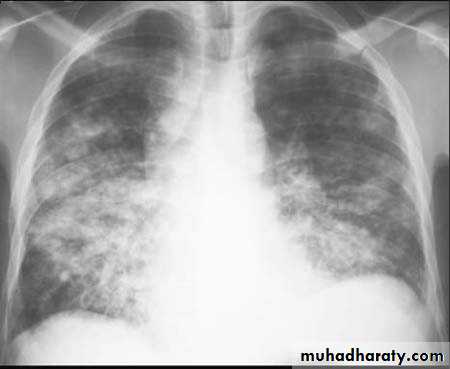

Bronchopneumonia: patchy alveolar consolidation associated with bronchial inflammation, often affecting lower lobes.

A chest X-ray is usually sufficient to confirm the clinical diagnosis of pneumonia.

Chest X-ray helps in:• Differentiating CAP from other diagnosis

• Provide information about severity (cavitation and multilobar involvement)

• Detects complications (pleural effusion or abscess formation).

• It can occasionally suggest an aetiological agent (pneumatocoele in Staphylococcus aureus pneumonia).